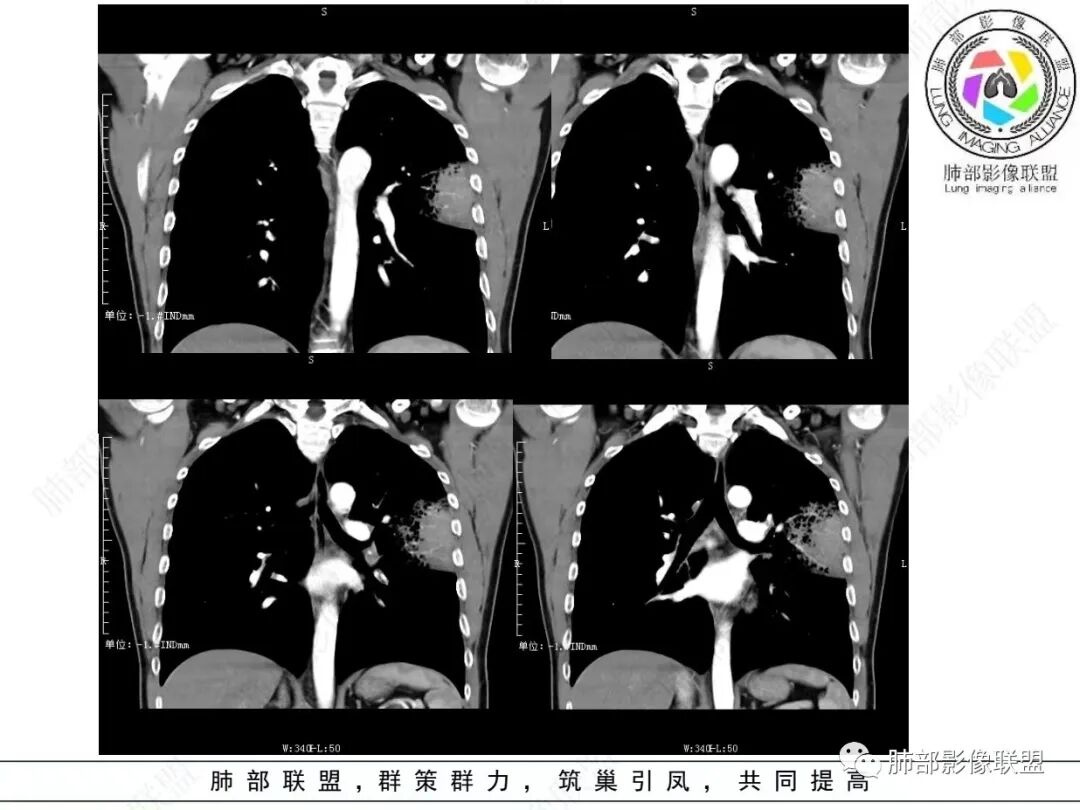

左肺上叶片状实变,内可见多发空泡及蜂窝影,斜裂上方可见相同病灶由于斜裂阻挡呈重力分布,强化可见血管造影征,双肺弥漫分布气腔结节,临床咳白色粘液痰,考虑粘液腺癌

男,46,咳嗽半年,加重10天,白粘痰,偶有痰血。胸部CT:左肺上叶舌叶大片实变影,边缘GGO,长轴沿胸膜及叶裂展开,重力依赖,胸膜叶裂阻隔,内见蜂窝,钱币征,枯枝。强化不均匀,血管造影征。考虑粘液腺癌,鉴别大叶性肺炎、干酪性肺炎等。

大片实变灶累及多个段

实变区位于胸膜下,长轴与胸膜平行

实变区内有低密度带,强化偏低,欠均匀

2.左肺上叶大片状混合密度影,未见空洞,实变影主要位于胸膜下,长轴与胸膜平行,实变区内部密度不均、其内可见多发小斑片状低密度影,磨玻璃影多位居肺门一侧,可见网格,磨玻璃影边界多可分辨,重力分布趋势。病灶区支气管显示较为通畅,进入外围实变区渐至消隐。病灶轻度不均匀低强化,病灶区肺动脉显示较良好,未见破坏。

双肺广泛分布微小磨玻璃密度结节影,腺泡结节样分布,密度大小较为均匀一致。